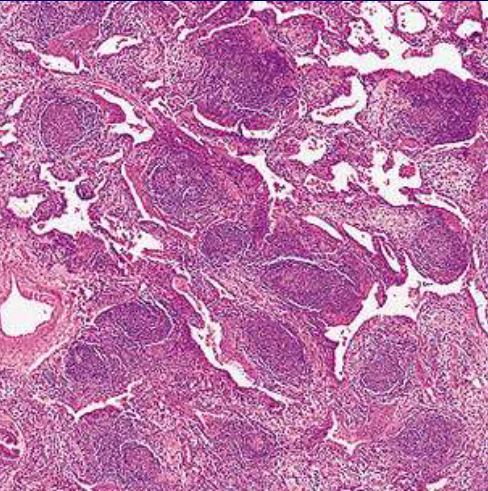

What process is shown here?

Centrilobular emphysema